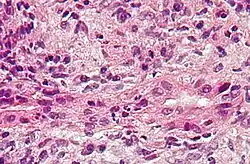

Description de cette image, également commentée ci-après

Coupe histologique d'une cholangite biliaire primitive montrant l'inflammation et la lésion des voies biliaires. Coloration à l'hématoxyline et à l'éosine.

La biopsie hépatique signe le diagnostic, mais est rarement pratiquée, surtout dans les cas où les anticorps anti-mitochondrie font défaut. L'examen histologique montre alors des lésions de cholangite et des altérations des voies biliaires interlobulaires[5].